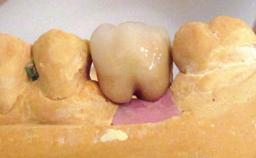

Peri-implantitis Resulting in Bisphosphonate-related Osteonecrosis of the Jaw

A 82-year-old female patient was referred to the Department of Oral Surgery and Stomatology at the University of Bern, Switzerland, for further diagnosis and treatment of growing discomfort in the right mandible (implant 45) and left maxilla (implant 23). The patient had had implants of various types inserted in the mandible and maxilla over the course of the previous three decades (in the 1980s and 1990s). The patient had received removable partial dentures on implants in the maxilla and on natural teeth in the mandible. The implants in the posterior right mandible had been restored with two splinted single crowns. The lower partial denture was not well tolerated by the patient and therefore had not been worn for over ten years. After insertion of the implants, there had been no complications for many years, but implants 45 and 46 as well as 23 had begun to exhibit signs of peri-implantitis with limited bone loss several years previously. The infection had been treated by the private practitioner, and bone loss around the three implants had not progressed until about half a year previously.